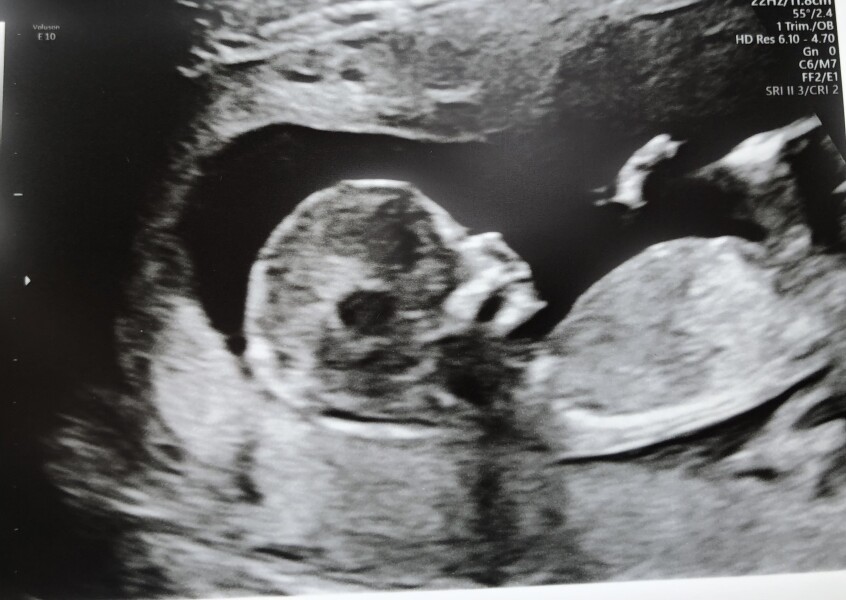

LolaJ87 · 03/06/2022 09:18

Things still aren’t running smoothly for me at all, but that meant another scan yesterday.

Anyone want to guess if it’s a boy or girl? I was 13+1 at the scan.

@LolaJ87 i have no idea but what a beautiful image!

@LolaJ87 what a gorgeous baby 🥰 I think that looks like a girl skull ❤️

@BuchananBaby thank you so much ❤It's wonderful to see them starting to look like their own little person.

@LolaJ87 I've got no clue but what an amazing scan pic 😍